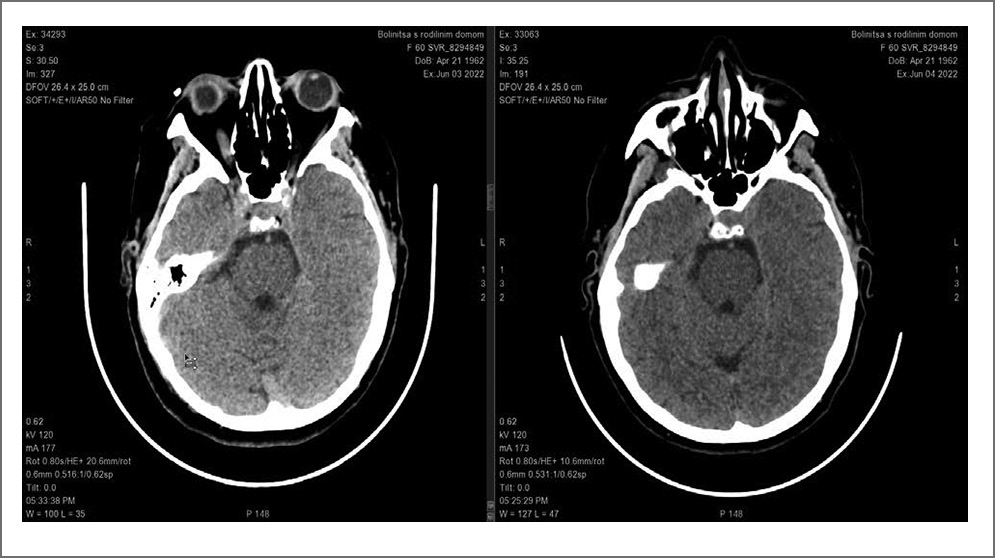

КТ: данных в пользу острых очаговых изменений в головном мозге не получено. Данные лабораторного контроля в границах референсных значений (рис. 6).

Рис. 6. КТ головного мозга пацентки С.

Через 20 мин от поступления проведен консилиум и принято решение о назначении СТЛТ препаратом Фортелизин® в соответствии с инструкцией (10 мг, растворенные в 10 мл физраствора, внутривенно струйно в течение 10 с).

При оценке состояния через 60 мин – состояние с положительной динамикой.

Сознание: ясное. Гемодинамика стабильная. Без дыхательных нарушений.

В неврологическом статусе оценка по шкалам: NIHSS (баллы): 1; ШКГ: 15; FOUR 16; Индекс активности Ривермид (баллы): 3; Шкала Рэнкин: 3 балла. При КТ-контроле через сутки данных в пользу острых очаговых изменений, объемных образований и геморрагического содержимого в головном мозге не получено.

При выписке оценка неврологического статуса по шкалам: NIHSS (баллы): 0; Индекс активности Ривермид (баллы): 12; Шкала Рэнкин: 1 балл.